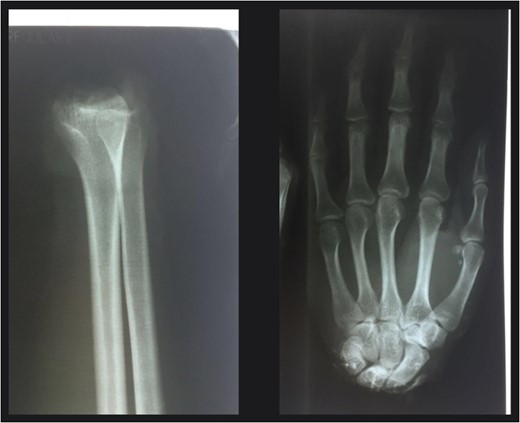

Thirty minutes after entry into the ER patient is taken into surgery, where he is given general anesthetic, and subjected to debridement and intense wash of the amputated hand and stump, using surgical soap Gluconate of Clorhexidine and sterile saline solution (10 L).

We proceed to insert K.W. 1.8 mm, running through the distal radius to the carpus (ulnar side) and another from the distal radius to the other side (radial side); once the bone stabilization was obtained, we proceed to identity the ulnar artery and regularize its walls, both of the stump as well as in the hand and we proceed to the anastomosis using nylon 9-0, placing simple separate stitches, clamp is liberated and good perfusion is evidenced; we then proceed to find a vein in the dorsal forearm and in the hand, we dissected the proximal segments and due to a deficit in length we decide to take a vein graft in the dorsal forearm (7 cm in longitude), this is interposed between the ends; we then performed an anastomosis with stitches using nylon 9-0, there was a good flow (venous return) when we released the clamps. We find the ulnar and median nerve stumps and we perform a nerve repair using single stiches with nylon 7-0 along the circumference of both nerves (Fig. 3).

Reimplantation of the hand, with adequate blood supply and reconstruction of tendons.

We then find the flexor and extensor tendons in the forearm and hand and we proceed to repair with Kestler type stitches using nylon 4-0. Skin closure with 4-0, on the radial side of the wrist, palmar side there is a defect of ~4 cm in diameter whereby it is necessary to take and place a full thickness graft for which we use the anterior side of the elbow as donor area.